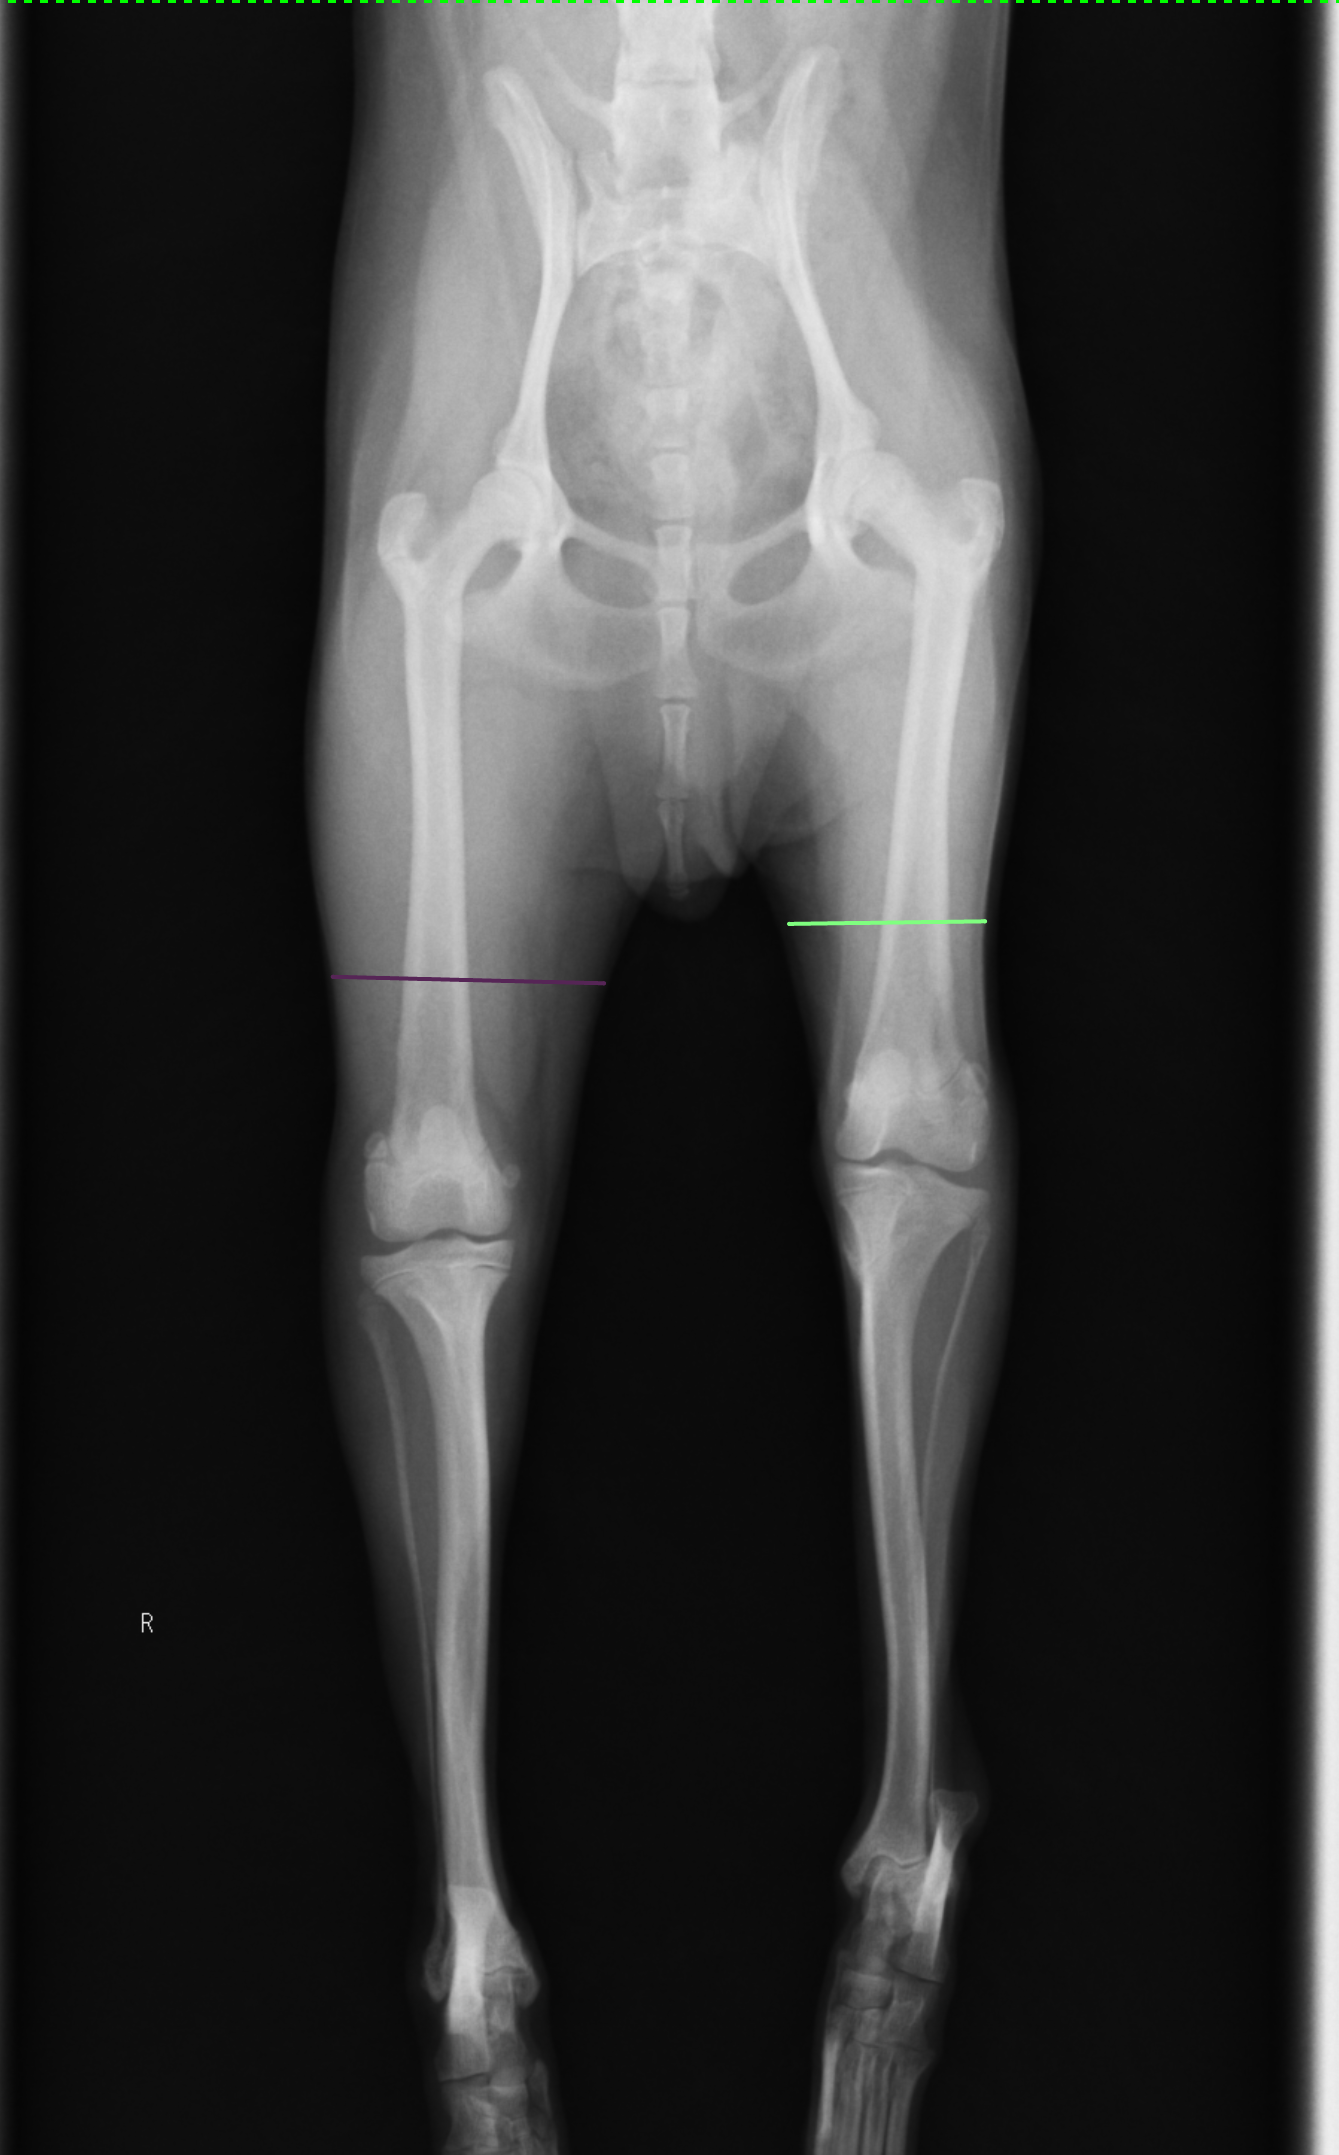

●左後肢に発症した1歳4ヶ月のトイプードルの症例(体重2.3kg)

右と比べて左後脚の跛行によって脚を使うことできないために筋肉の付きが明らかに減ってしまっています。